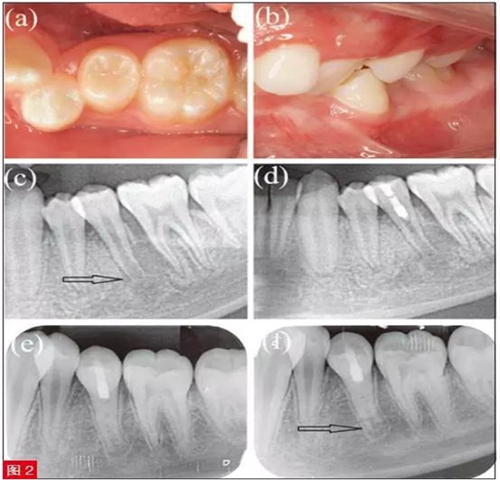

患者為11 歲男童,主訴左下后牙疼痛腫脹3天,近日出現(xiàn)多次陣發(fā)痛,故前來就診。臨床檢查,見左下第二前磨牙畸形中央尖折斷。35 牙冷測和EPT 測試均無反應(yīng),而鄰牙34、36 反應(yīng)正常。35 叩診(+),I度松動,頰側(cè)根尖區(qū)牙齦隆起伴壓痛,牙周探診正常。根尖片示35 牙根未發(fā)育完全,根尖孔敞開且根尖周有明顯透射影(圖2c)。

對35 進行臨床和影像檢查,初步診斷為有癥狀的根尖周炎。面開髓后,可觀察到根管中段近冠方處有粉色、質(zhì)地連續(xù)的活髓組織,最終診斷為35 牙部分牙髓壞死伴有癥狀的根尖周炎。隨即對該患牙進行部分牙髓切斷術(shù)。治療過程與病例1 相仿(圖2d)。

患者6 個月后隨訪,根尖片示35 根尖周透射影完全消失(圖2e)。8 個月后復(fù)查,患者癥狀完全消除,偶遇熱水會出現(xiàn)一過性敏感。根尖片示根尖周組織愈合,牙根長度和根管壁厚度均明顯增加(圖2f),且無任何臨床癥狀和體征(圖2a 和2b)?;佳览錅y和EPT測試均顯示牙髓有活力,其中EPT 值為31,與鄰牙36的EPT 值21 相近。